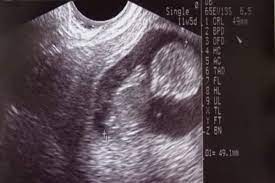

A nuchal scan or nuchal translucency ( nt) scan / procedure is a sonographic prenatal screening scan ( ultrasound) to detect chromosomal abnormalities in a fetus, though altered extracellular matrix composition and limited lymphatic drainage can also be detected. The number of fetuses and gestation sacs. This is between 11 weeks and 13 weeks plus six days, to be exact (nice 2008), or when your baby's crown rump length (crl) is between 45mm (1.8in) and 84mm (3.3in). Google's free service instantly translates words, phrases, and web pages between english and over 100 other languages. They had indeed a word for such happenings. Tamil is also an official spoken language in sri l anka & singapore. So the nt scan will usually happen alongside your routine dating scan. Tamil is a very old classical language and has inscriptions from 500 b.c and plays a significant role as a language in the world today.

This is between 11 weeks and 13 weeks plus six days, to be exact (nice 2008), or when your baby's crown rump length (crl) is between 45mm (1.8in) and 84mm (3.3in). You can discuss whether you want or need a dating scan with your doctor or midwife. Check 'anomaly' translations into tamil. You can also listen to your baby's heartbeat during this scan. A nuchal scan or nuchal translucency ( nt) scan / procedure is a sonographic prenatal screening scan ( ultrasound) to detect chromosomal abnormalities in a fetus, though altered extracellular matrix composition and limited lymphatic drainage can also be detected. A dating scan might be recommended before 12 weeks to confirm your due date if you are unsure of your last menstrual period or your date of conception. The sonographer will measure the baby and use these measurements. The presence of a heart beat.